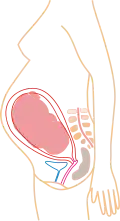

Stadia in beeld

- (aantal maanden refereert aan PML)

4 maanden 5 maanden

5 maanden 6 maanden